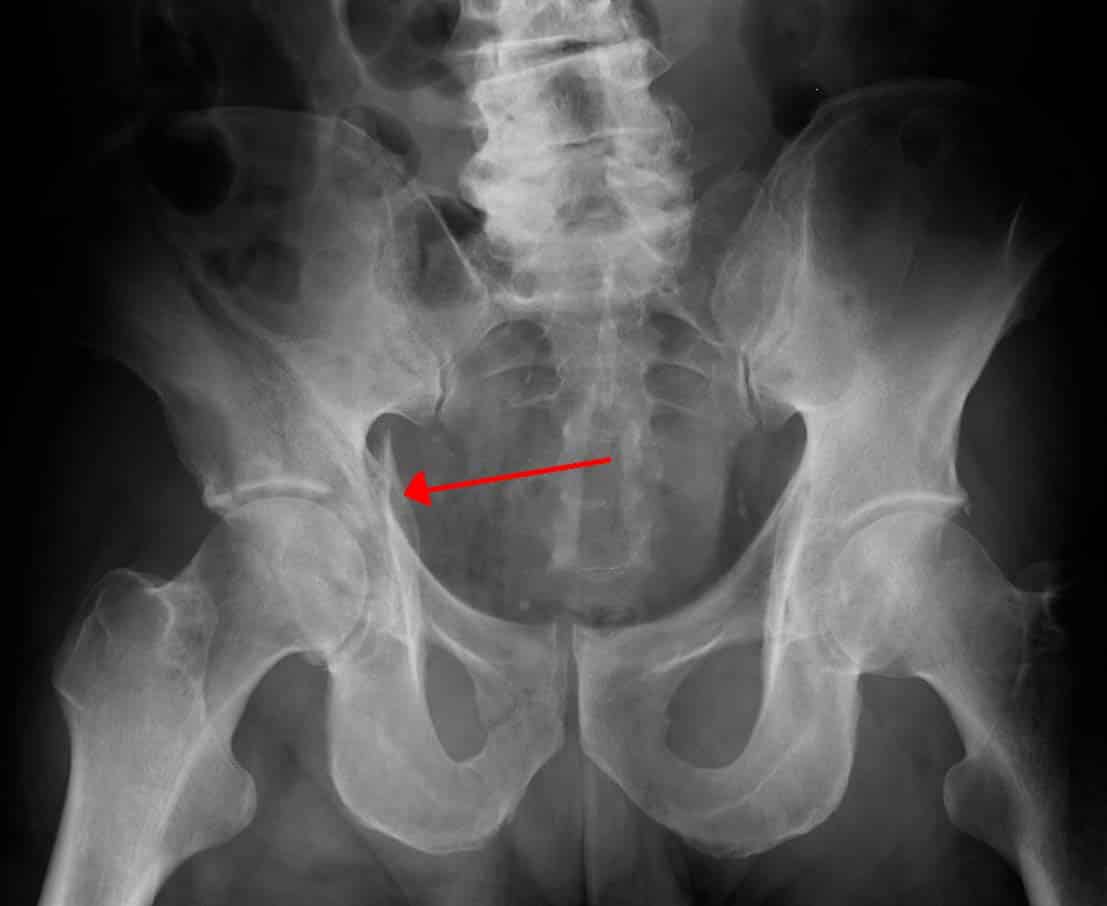

The left and right hip bones (innominate bones, pelvic bones) are two irregularly shaped bones that form part of the pelvic girdle – the bony structure that attaches the axial skeleton to the lower limbs. The hip bones have three main articulations: Sacroiliac joint – articulation with the sacrum. Pubic symphysis – articulation between the left and right hip bones. Hip joint – articulation with the head of femur. In this article, we shall look at the anatomy of the hip bones – their composition, bony landmarks, and clinical relevance. By Anatomography [CC-BY-SA-2.1-jp], via Wikimedia Commons Fig 1Overview of the anatomical position of the hip bones. Pro Feature - 3D Model You've Discovered a Pro Feature Access our 3D Model Library Explore, cut, dissect, annotate and manipulate our 3D models to visualise anatomy in a dynamic, interactive way. Learn More Composition of the Hip Bone The hip bone is comprised of the three parts; the ilium, pubis and ischium. Prior to puberty, the triradiate cartilage separates these parts – and fusion only begins at the age of 15-17. Together, the ilium, pubis and ischium form a cup-shaped socket known as the acetabulum (literal meaning in Latin is ‘vinegar cup‘). The head of the femur articulates with the acetabulum to form the hip joint. We shall now look at the individual parts of the hip bone, and their respective bony landmarks. By TeachMeSeries Ltd (2025) Fig 2The hip bone of a 5 year old, with triradiate cartilage still present. The Ilium The ilium is the widest and largest of the three parts of the hip bone, and is located superiorly. The body of the ilium forms the superior part of the acetabulum (acetabular roof). Immediately above the acetabulum, the ilium expands to form the wing (or ala). The wing of the ilium has two surfaces: Inner surface – has a concave shape, which produces the iliac fossa (site of origin of the iliacus muscle). External surface (gluteal surface) – has a convex shape and provides attachments to the gluteal muscles. The superior margin of the wing is thickened, forming the iliac crest. It extends from the anterior superior iliac spine (ASIS) to the posterior superior iliac spine (PSIS). On the posterior aspect of the ilium there is an indentation known as the greater sciatic notch. By TeachMeSeries Ltd (2025) Fig 3The bony landmarks of the ilium. Clinical Relevance Anterior Superior Iliac Spine The anterior superior iliac spine (ASIS) is an important anatomical landmark: Mid-inguinal point – halfway between the ASIS and the centre of the pubic symphysis. The femoral artery can be palpated here. Mid-point of the inguinal ligament – halfway between the ASIS and the pubic tubercle. In clinical practice, a patient’s “true” leg length is measured from the ASIS to the medial malleolus at the ankle joint. This is distinct from “apparent” leg length, which is measured from the umbilicus to the medial malleolus. True leg length discrepancy is a feature of various hip disorders, as well as being a potential complication of hip joint replacement (arthroplasty). The Pubis The pubis is the most anterior portion of the hip bone. It consists of a body, superior ramus and inferior ramus (ramus = branch). Pubic body – located medially, it articulates with the opposite pubic body at the pubic symphysis. Its superior aspect is marked by a rounded thickening (the pubic crest), which extends laterally as the pubic tubercle. Superior pubic ramus – extends laterally from the body to form part of the acetabulum. Inferior pubic ramus – projects towards the ischium. Together, the superior and inferior rami enclose part of the obturator foramen – through which the obturator nerve, artery and vein pass through to reach the lower limb. By TeachMeSeries Ltd (2025) Fig 4Bony landmarks of the pubis. By TeachMeSeries Ltd (2025) Fig 5The orientation of the hip bones within the pelvis. Clinical Relevance Pubic Rami Fractures Pubic rami fractures can sometimes be observed on x-rays in elderly patients who are investigated after simple low energy falls from standing height. In this context and provided they are the only injury a patient has sustained, these fractures are usually treated without surgery. Healing can be expected within 6-8 weeks and patients are encouraged to fully weight bear straightaway. The Ischium The ischium forms the posteroinferior part of the hip bone. Much like the pubis, it is composed of a body, an inferior ramus and superior ramus. The inferior ischial ramus combines with the inferior pubic ramus forming the ischiopubic ramus, which encloses part of the obturator foramen. The posterorinferior aspect of the ischium forms the ischial tuberosities and when sitting, it is these tuberosities on which our body weight falls. Near the junction of the superior ramus and body is a posteromedial projection of bone; the ischial spine. Two important ligaments attach to the ischium: Sacrospinous ligament – runs from the ischial spine to the sacrum, thus creating the greater sciatic foramen through which lower limb neurovasculature (including the sciatic nerve) transcends. Sacrotuberous ligament – runs from the sacrum to the ischial tuberosity, forming the lesser sciatic foramen. Read more about the greater and lesser sciatic foramen here. By TeachMeSeries Ltd (2025) Fig 6Bony landmarks of the ischium. Clinical Relevance Pelvic Fractures There are two broad groups of pelvic fractures: Low energy injuries: For example, a simple fall from standing height in an osteoporotic patient resulting in pubic rami fracture. These are usually ‘stable’ injuries, not requiring surgery. High energy injuries with direct or transmitted trauma: For example, after a high speed road traffic accident. These result in more extensive fractures which may include the acetabulum and sacroiliac joint. These can be ‘unstable’ injuries and may require urgent surgery. Higher energy injuries can be associated with soft tissue and vascular injury. In particular, the bladder and urethra are at high risk of damage. Vascular injury can result in life threatening haemorrhage. In the context of a high energy major trauma patient, the pelvis can be a major source of bleeding due to fracture. As a result, major trauma patients are assumed to have a pelvic fracture until proven otherwise and a ‘pelvic binder’ is used to stabilise the pelvis and minimise further bleeding. Circumferential pressure is applied by the binder at the level of the greater trochanters – an important anatomical landmark. By James Heilman, MD [CC-BY-SA-3.0], via Wikimedia Commons Fig 7X-Ray demonstrating an acetabular fracture (arrow). Do you think you’re ready? Take the quiz below Pro Feature - Quiz The Hip Bone Question 1 of 3 Submitting... Skip Next Rate question: You scored 0% Skipped: 0/3 1800 More Questions Available Upgrade to TeachMeAnatomy Pro Challenge yourself with over 1800 multiple-choice questions to reinforce learning Learn More Rate This Article